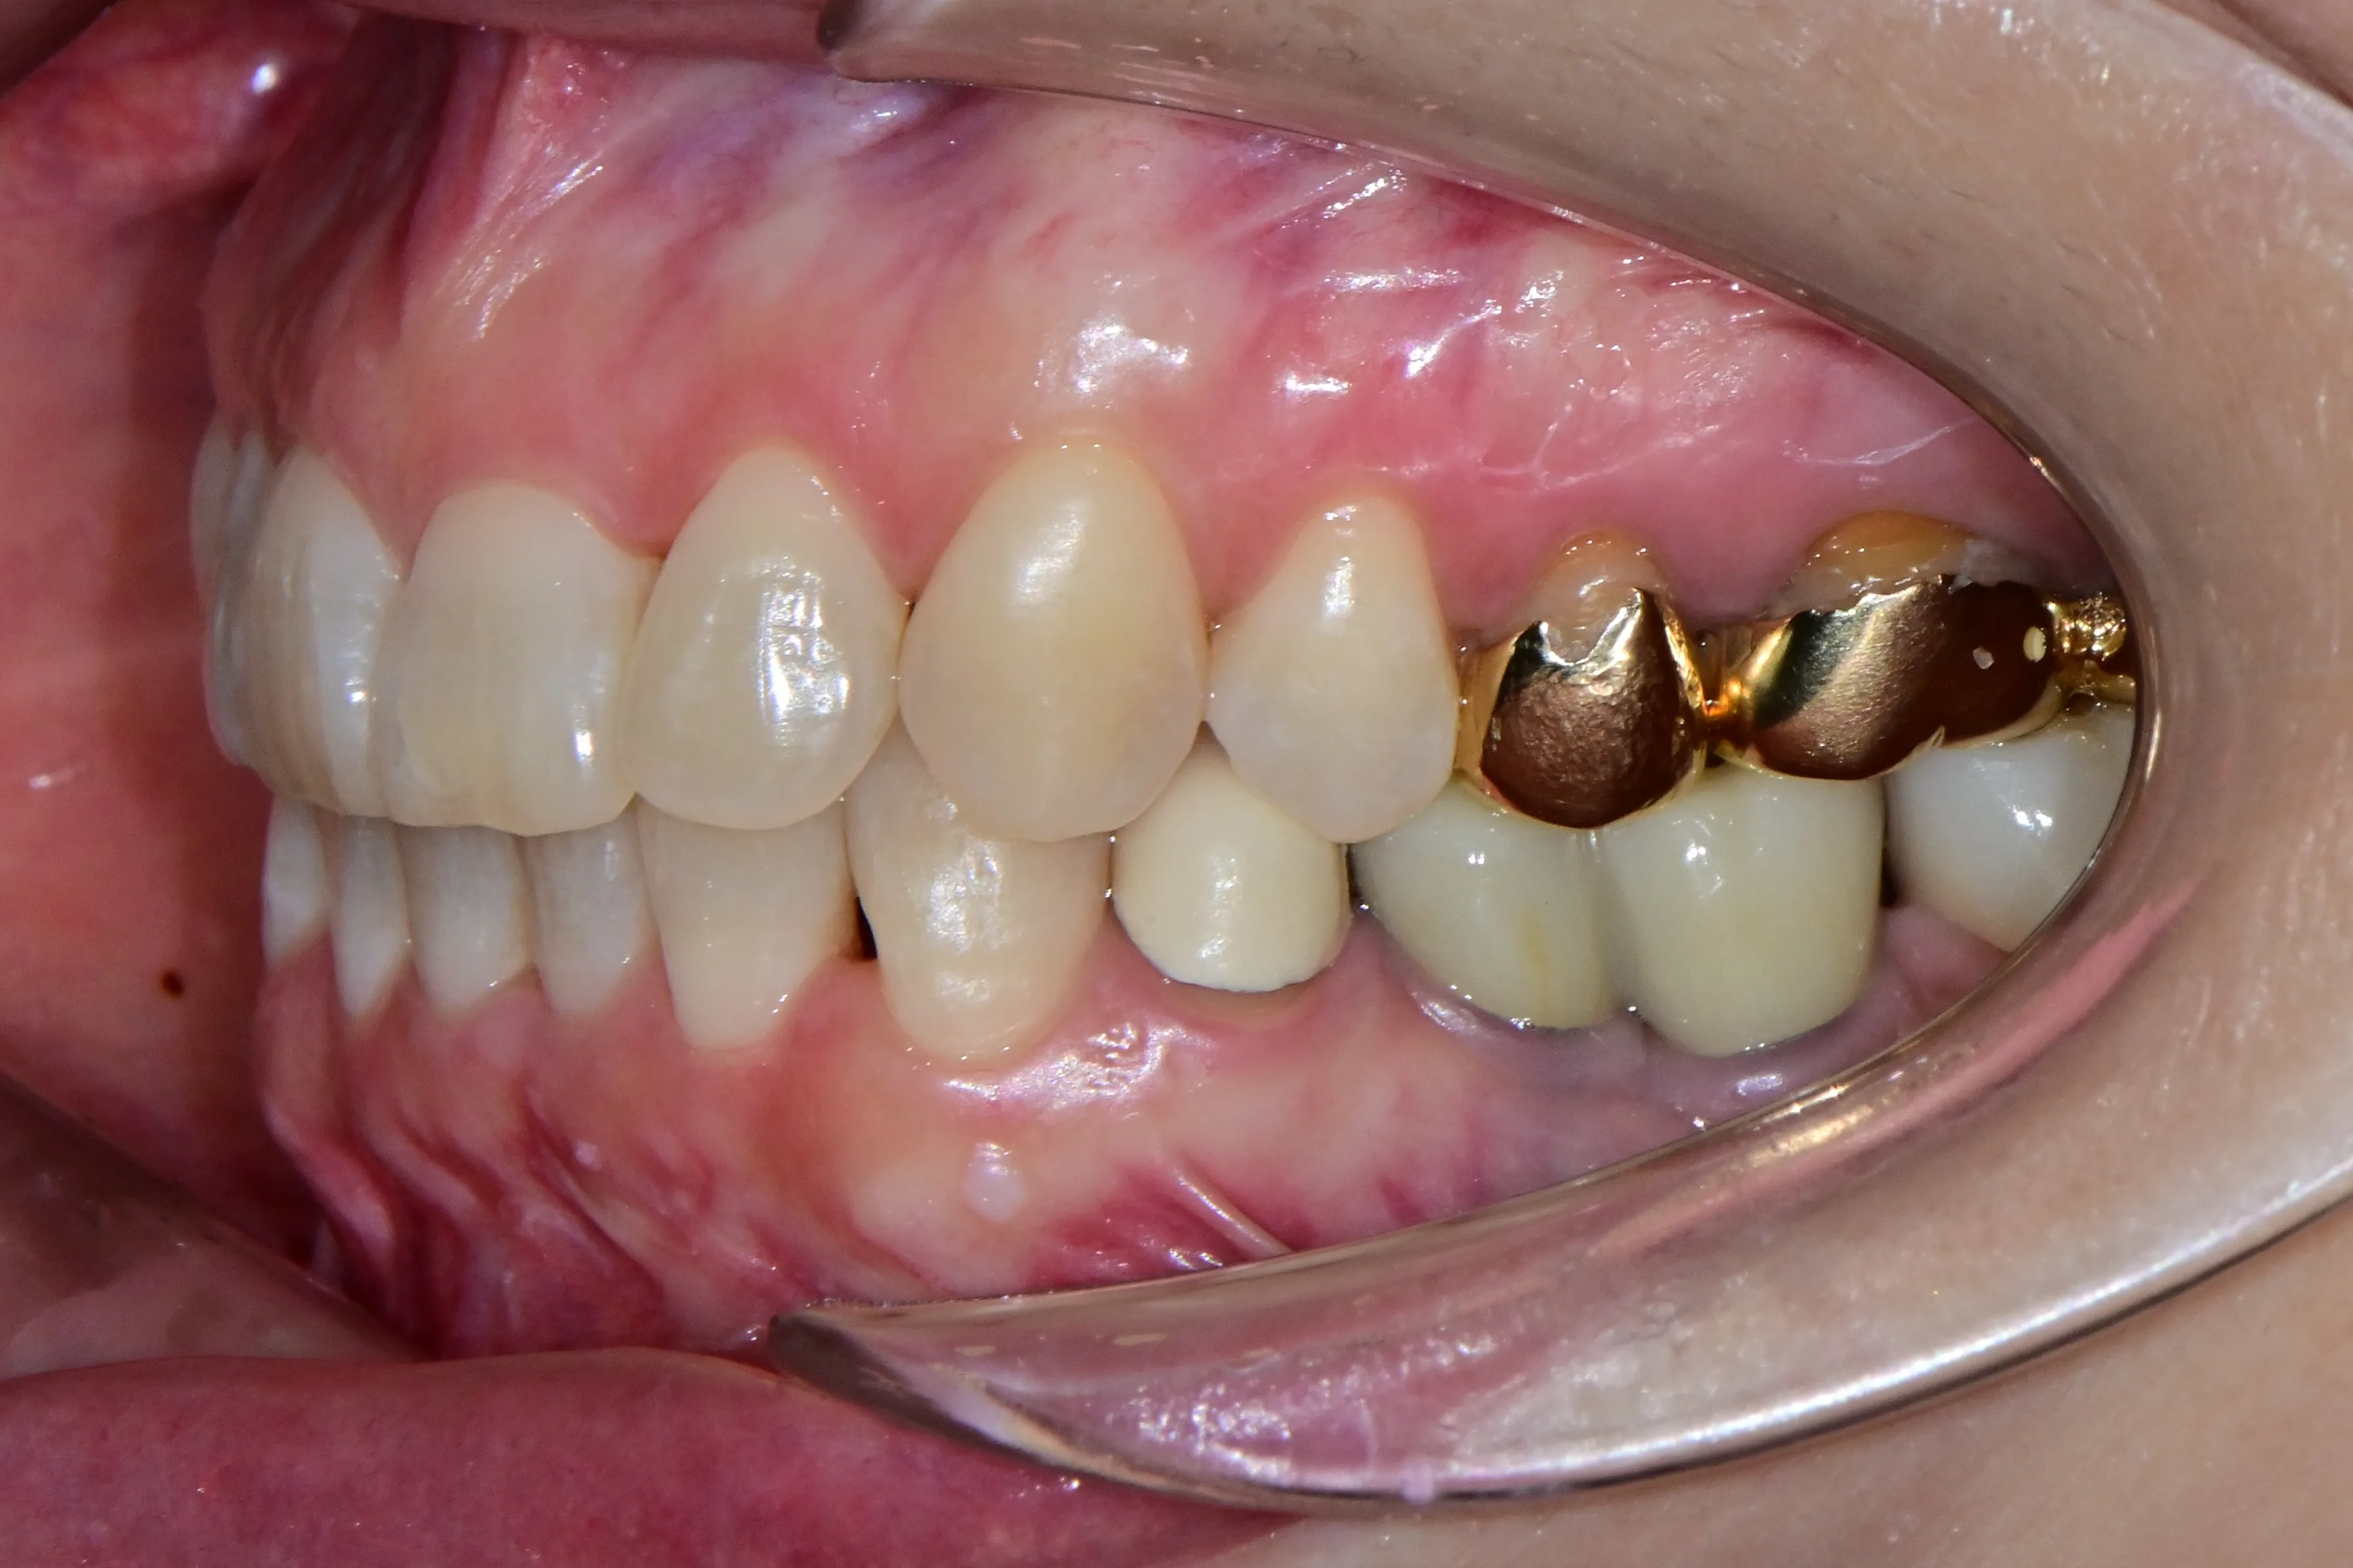

이 환자분은 이미 구강 안에 여러 개의 임플란트와 브릿지 보철물이 있는 상태였습니다. 앞니는 가지런하지 않고, 윗니가 아랫니를 깊게 덮는 과개교합(deepbite)도 있었습니다. 이런 경우 가장 중요한 것은 기존 임플란트와 보철물의 교합을 그대로 유지하면서, 나머지 치아만 가지런하게 배열하는 것입니다.

인비절라인의 디지털 치료 계획을 활용해서, 임플란트와 보철물이 있는 어금니는 움직이지 않도록 고정하고 앞니 위주로만 이동시켰습니다. 덕분에 발치 없이, 고무줄이나 미니스크류 같은 추가 장치 없이도 15개월 만에 치료를 마무리할 수 있었습니다.